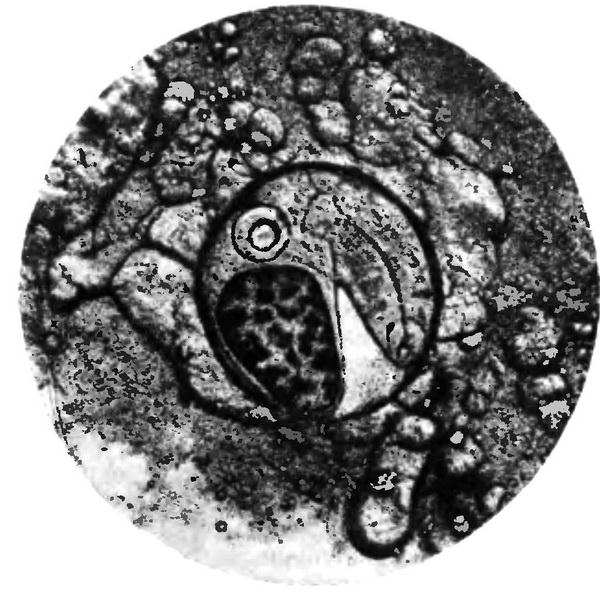

Рис. 4.5. Личинка описторха (метацеркарий), выделенная из рыбы (х60).

В организме водных моллюсков (Bithynia), проглотивших яйца, развиваются личинки – церкарии. Развитие их продолжается менее 2 мес. Затем церкарии выходят в воду, активно проникают в тело карповых рыб (язь, елец, плотва и др.), где в мышцах превращаются в следующую, инвазионную (заразную) личинку – метацеркарий, покрытую оболочкой (рис. 4.5). У метацеркариев сибирского сосальщика на тонком переднем конце видны шипики, а также крупные экскреторный пузырь черного цвета, овальный или слегка лопастной, ротовая и брюшная присоски, петли кишечника. Размер личинок 0,23–0,37 мм.